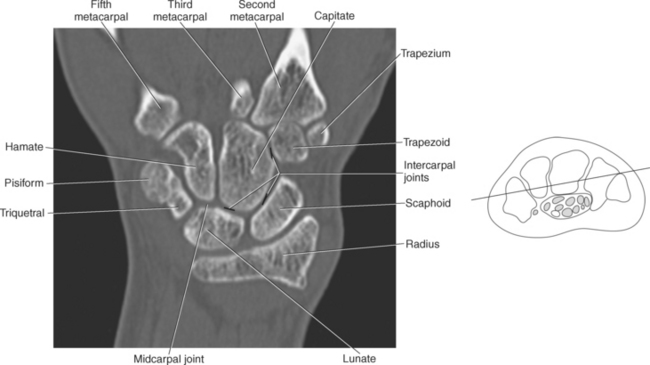

The bony anatomy of the wrist and hand consists of the distal radius and ulna, 8 carpal bones, 5 metacarpals, and 14 phalanges (Figure 9.101). Both the distal radius and ulna have a conical styloid process that acts as an attachment site for ligaments. The radial styloid process is located on the lateral surface of the radius, whereas the ulnar styloid process is located on the posteromedial side of the ulna. The carpal bones are arranged in proximal and distal rows. Located in the proximal row of carpal bones are the scaphoid (navicular), lunate (semilunar), triquetral (triquetrum), and pisiform bones. The pisiform is considered a sesamoid bone that is embedded in the tendon of the flexor carpi ulnaris. The distal row consists of the trapezium (greater multangular), trapezoid (lesser multangular), capitate (os magnum), and hamate (unciform) bones (Figures 9.102 through 9.114). The five metacarpals are small tubular bones with a proximal end (base), distal end (head), and shaft (body). The 14 phalanges that make up the fingers are short tubular bones. Like the metacarpals, each phalanx consists of a proximal (base), middle (body or diaphysis), and distal (head) portion. Each digit consists of 3 phalanges (proximal, middle, and distal), except for the thumb (first digit), which has only 2 phalanges (proximal and distal). The articulation of the phalanges of the second through fifth digits creates three interphalangeal joints: the metacarpophalangeal (MCP) joints classified as condyloid joints, proximal interphalangeal (PIP), and distal interphalangeal (DIP). The proximal and distal interphalangeal joints are classified as hinge joints (Figure 9.101). The first digit, which consists of 2 phalanges, has just two joints: the MCP joint, classified as a saddle joint, and an interphalangeal joint, classified as a hinge joint (Figure 9.101).

The joints of the wrist and hand are quite complex and consist of the following: distal radioulnar articulation, radiocarpal articulation (proximal joint of hand), midcarpal articulation (distal joint of hand), intercarpal articulations (articulations between proximal and distal carpals), carpometacarpal articulations (between carpals and metacarpals), the intermetacarpal articulations (between bases of metacarpals two through five) and the interphalangeal joints (between phalanges of each digit) (Figures 9.111 and 9.115). The distal radioulnar articulation, also called the distal radioulnar joint (DRUJ), is created when the ulnar notch of the radius moves around the articular circumference of the ulna, providing the movements of supination and pronation. The main stabilizing element of the DRUJ is an articular disk called the triangular fibrocartilage complex (TFCC). The TFCC is a fan-shaped band of fibrous tissue that originates on the medial surface of the distal radius and traverses horizontally to insert on the ulnar styloid process (Figures 9.115 and 9.116). It rotates against the distal surface of the ulnar head during pronation and supination and separates the ulna from the carpal bones. The proximal surface of the radiocarpal articulation is formed by the articular carpal surface of the radius and the TFCC, whereas the distal surface is formed by the articular surfaces of the scaphoid, lunate, and triquetrum and the interosseous ligaments connecting them (Figures 9.111 through 9.115). The midcarpal joint is formed by the articulations between the proximal and distal carpal rows (Figures 9.110 and 9.115). The articulation between the carpals within each row creates the intercarpal joints (Figures 9.111 and 9.115). The carpometacarpal joints are formed by the articulations between the carpus and the five metacarpals (Figure 9.111 and 9.115). The carpometacarpal joint of the thumb is an independent joint formed by the articular surfaces of the trapezium and first metacarpal, creating a pure saddle joint. The carpometacarpal articulations of the two to five digits are amphiarthrotic joints with little mobility (Figures 9.105 and 9.115). The intermetacarpal articulation exists between the base of the metacarpals and is joined by the palmar and dorsal metacarpal ligaments (Figure 9.115).

Numerous ligaments provide additional stability to the wrist. The extrinsic ligaments reinforce the joint cavity surrounding the carpal region and include palmar and dorsal radial carpal ligaments, the radial and ulnar collateral ligaments, and the TFCC (Figures 9.115 through 9.117). The many articulations between the carpal bones are supported by the intercarpal ligaments or intrinsic ligaments that connect the carpal bones to each other (Figure 9.115). The configuration of the intrinsic ligaments, metacarpal ligaments, and triangular fibrocartilage complex creates five different joint compartments that can be demonstrated at arthrography: (1) compartment of the first carpometacarpal articulation, (2) common carpometacarpal compartment, (3) mediocarpal compartment, (4) intermetacarpal compartment, and (5) radiocarpal compartment (Figure 9.115). The carpal tunnel is created by the concave arrangement of the carpal bones (Figure 9.103). A thick ligamentous band called the flexor retinaculum (transverse carpal ligament) stretches across the carpal tunnel to create an enclosure for the passage of tendons and the median nerve (Figures 9.118 through 9.120). The flexor retinaculum inserts medially on the pisiform and hook of the hamate and spans the wrist to insert laterally on the scaphoid and trapezium. In addition to the carpal tunnel, another tunnel called Guyon’s canal is formed where the ulnar extension of the flexor retinaculum continues over the pisiform and hamate. This creates a potential site for compression of the ulnar nerve (Figures 9.118, top, and 9.119). The extensor retinaculum (dorsal carpal ligament), located dorsally, is much thinner. It attaches medially to the ulnar styloid process, triquetrum, and pisiform and laterally to the lateral margin of the radius (Figure 9.120, left). Along its course it forms six fibroosseous tunnels for the passage of the synovial sheaths containing the extensor tendons (Figure 9.118, bottom).